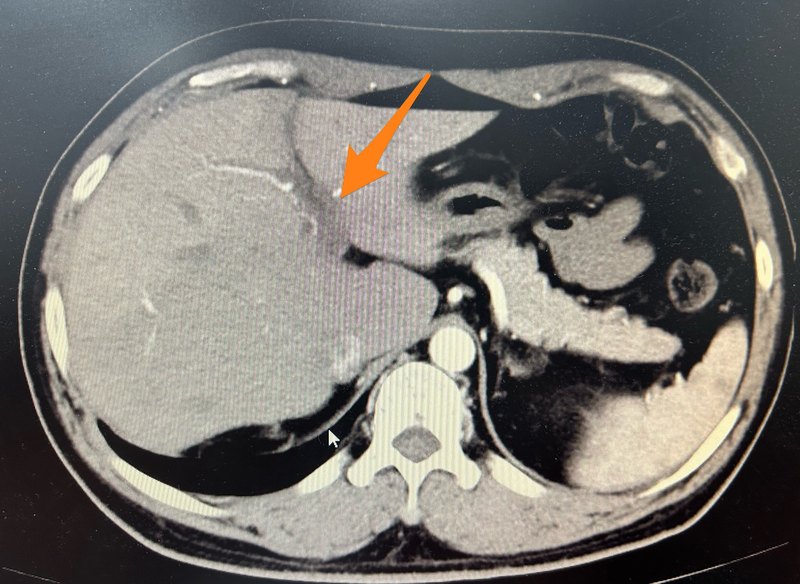

抗凝聯(lián)合經(jīng)腸系膜上動(dòng)脈置管溶栓治療彌漫門脈血栓案例分享

患者中年男性,因?yàn)楦雇锤姑?天,加重1天到我院急診科求診,急診超聲及ct提示門脈左右支主干、脾靜脈及腸系膜上靜脈血栓形成。門脈左支血栓形成。門脈右支血栓形成。門脈主干及脾靜脈血栓形成。腸系膜上靜脈血栓形成??鼓惶旌蟾雇窗Y狀稍有緩解,2023.9.26行經(jīng)腸系膜上動(dòng)脈置管溶栓治療,尿激酶25萬U,q6h,2023.10.1拔管,繼續(xù)經(jīng)靜脈溶栓治療,尿激酶25萬U,q8h,患者肝素過敏,溶栓期間利伐沙班15mg,bid。10月7復(fù)查ct,門脈脾靜脈及腸系膜上靜脈血栓變化不明顯,但是患者腹痛腹脹癥狀基本消失,可正常進(jìn)食及排便,給予出院繼續(xù)口服利伐沙班抗凝治療。2023.11.14患者復(fù)查ct,提示門靜脈、脾靜脈及腸系膜上靜脈血栓大部分消失,門脈主干仍然殘存少許血栓。門脈左支血栓基本消失。門脈右支血栓基本消失。腸系膜上靜脈血栓基本消失。脾靜脈血栓基本消失。門脈主干似有少許血栓殘余。繼續(xù)密切觀察,繼續(xù)抗凝治療,利伐沙班20毫克,qd。點(diǎn)評(píng):門脈血栓臨床多見,治療方案選擇也存在一定的爭議,我們既往采取抗凝治療聯(lián)合經(jīng)腸系膜上動(dòng)脈置管溶栓治療不同程度門脈血栓患者均取得良好效果。此患者就診時(shí)候血栓負(fù)荷極大且腹脹腹痛癥狀明顯,隨時(shí)有腸壞死風(fēng)險(xiǎn),采取腸系膜上動(dòng)脈置管溶栓加抗凝的方案是否可以取得良好療效術(shù)前其實(shí)我們并沒有很大的把握。我們和患者充分溝通各種治療方案后,患者愿意選擇先嘗試這個(gè)治療方案,但是治療12天后雖然患者癥狀基本消失,但是復(fù)查增強(qiáng)ct,血栓變化并不明顯,這個(gè)時(shí)候如何選擇下一步治療方案,也會(huì)存在較大的分歧,我們和患者充分溝通后采取耐心抗凝的方案,一個(gè)月后復(fù)查提示血栓基本消失,這個(gè)案例或許提示即使在血栓負(fù)荷很重的患者采取這個(gè)方案依然可能取得滿意的療效,值得更多嘗試。對(duì)于門脈血栓負(fù)荷較重的患者,介入同道曾嘗試經(jīng)皮經(jīng)肝穿刺取栓及置管溶栓的方案,近年來也有不少同道采取直接tips通道抽栓及溶栓的方案,這兩個(gè)方案風(fēng)險(xiǎn)費(fèi)用均遠(yuǎn)高于經(jīng)腸系膜上動(dòng)脈置管溶栓,但是效果是否優(yōu)于經(jīng)腸系膜上動(dòng)脈置管溶栓仍然存在爭議。根據(jù)肝硬化門靜脈血栓管理專家共識(shí)(2020年,上海)引用一項(xiàng)隨機(jī)對(duì)照試驗(yàn)比較了經(jīng)腸系膜上動(dòng)脈持續(xù)泵入尿激酶(劑量為15000IU·kg?1·d?1)與TIPS治療肝硬化PVT的療效差異,雖然兩組間的門靜脈主干血栓的再通率相近,但溶栓組的腸系膜上靜脈及脾靜脈血栓的再通率顯著高于TIPS組,且肝性腦病發(fā)生率明顯更低。提示該共識(shí)意見似乎更傾向于推薦采取經(jīng)腸系膜上動(dòng)脈置管溶栓的方案。